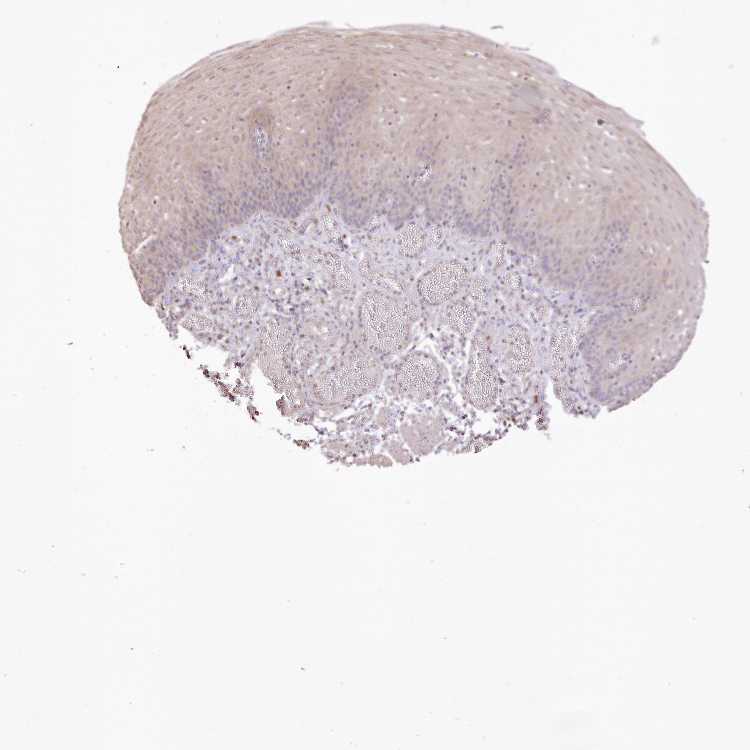

ESOPHAGUS - Antibody stainingi

Antibody staining in the annotated cell types in the current human tissue is reported as not detected, low, medium, or high, based on conventional immunohistochemistry profiling in selected tissues. This score is based on the combination of the staining intensity and fraction of stained cells.

Each image is clickable and will lead to virtual microscopy that enables deeper exploration of all samples and also displays staining intensity scores, fraction scores and subcellular localization as well as patient and tissue information for each sample.

Antibody HPA068982Antibody CAB032885

Squamous epithelial cells Not detectedMedium